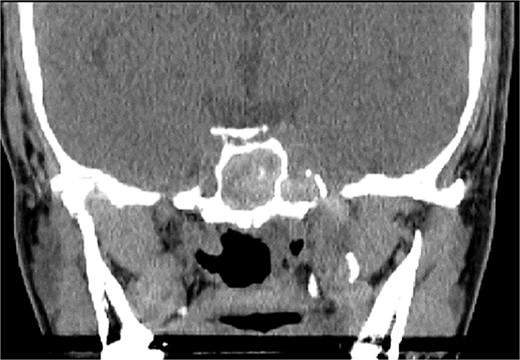

An asthmatic 42-years-old patient who was previously medically treated for allergic rhinitis with no significant improvement. A subsequent CT scan revealed isolated sphenoid sinus disease (Fig. 3). Intra-operative endoscopic findings revealed fungal mud and mucin (Fig. 4A and B) with post-operative (Fig. 4C) endoscopic finding of widely open, clean sphenoid sinus. Further histological examination of the specimen proved the diagnosis of eosinophilic AFS.

Coronal CT scan image showing complete sphenoid sinus heterogenous opacification.